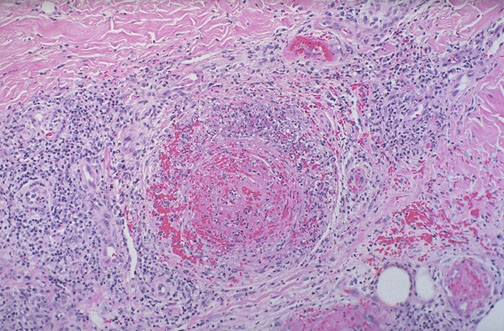

This is a case of polyarteritis nodosa (PAN) seen in dermis at low magnification.